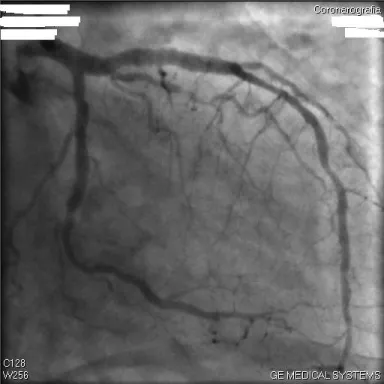

12 hours after admission, cardiac catheterization was performed and revealed a stenosis of 60% on proximal left anterior descending (LAD) (figure 1), a stenosis of 60 % on the circumflex coronary (CX)(figure 1) and a stenosis of 70 % on the right coronary artery (RCA) with a ulcerated plaque (figure 2). A IVUS chromaflow control showed rupture ulcerated atheromatous plaque on LAD (figure 3) and a fibrolipidic plaque with necrotic areas on CX (figure 4). Due to the clinical instability of the patient and of the presence of vulnerable plaques, the three lesions were treated by percutaneous coronary intervention, with the use of a Sirolimus eluting coronary stent, 3,5x23 mm, on LAD, a sirolimus eluting coronary stent, 2,7x18 mm, on CX (figure 5) and a sirolimus eluting coronary stent, 3x25 mm, on right artery coronary (figure 6). The results were excellent with a TIMI (thrombolysis in myocardial infarction) 3 score resultant flow. On discharge, the ECG showed negative T waves from V1 to V4. We recommended long term antiplatelet therapy, including aspirin and clopidogrel. 12 months later, follow up evaluation revealed that the patient was asymptomatic, the ECG was normal and ECG stress test didn’t show any markers of myocardial ischemia.

Instead coronary angiography may reveal advanced lesions, plaque disruption, luminal thrombosis and calcification, but other qualitative features of the underlying plaque cannot be assessed by this imaging technique. Visualization of the vessel wall and the plaque itself rather than the lumen is possible with intravascular ultrasound (IVUS), that reveal the characterization of coronary plaques.